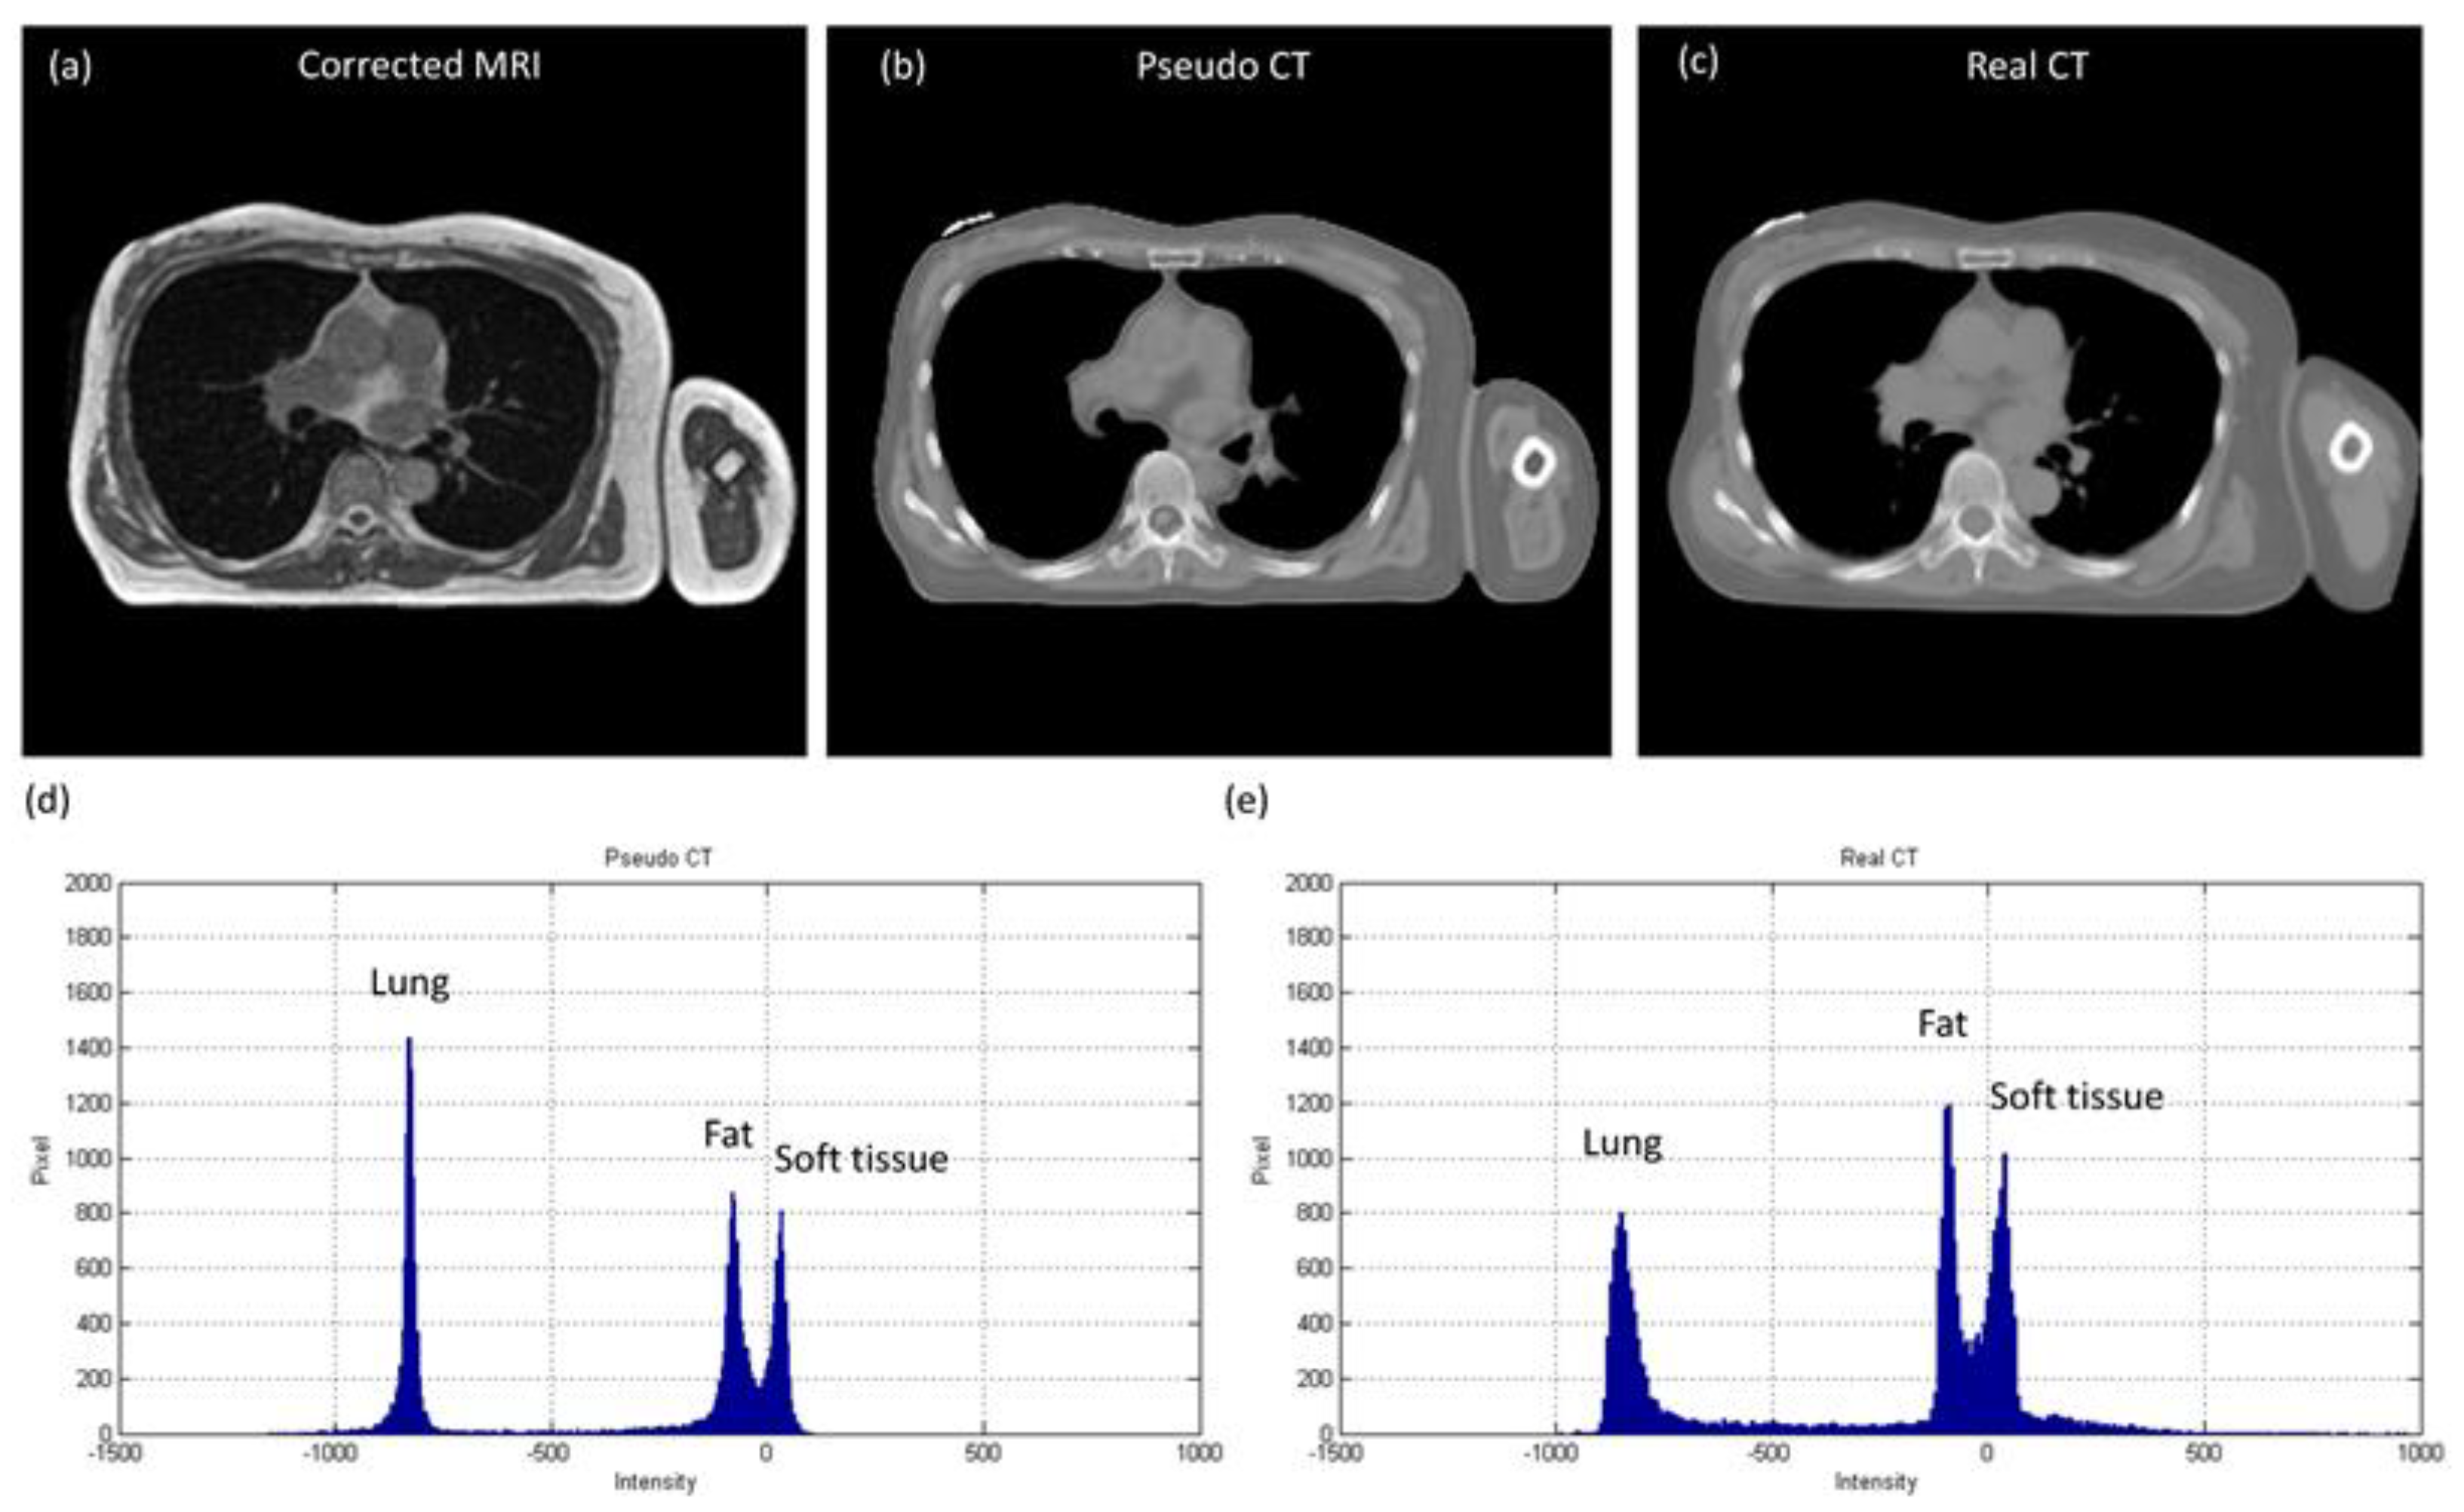

3.1. Chest Imaging for Cancer Treatment